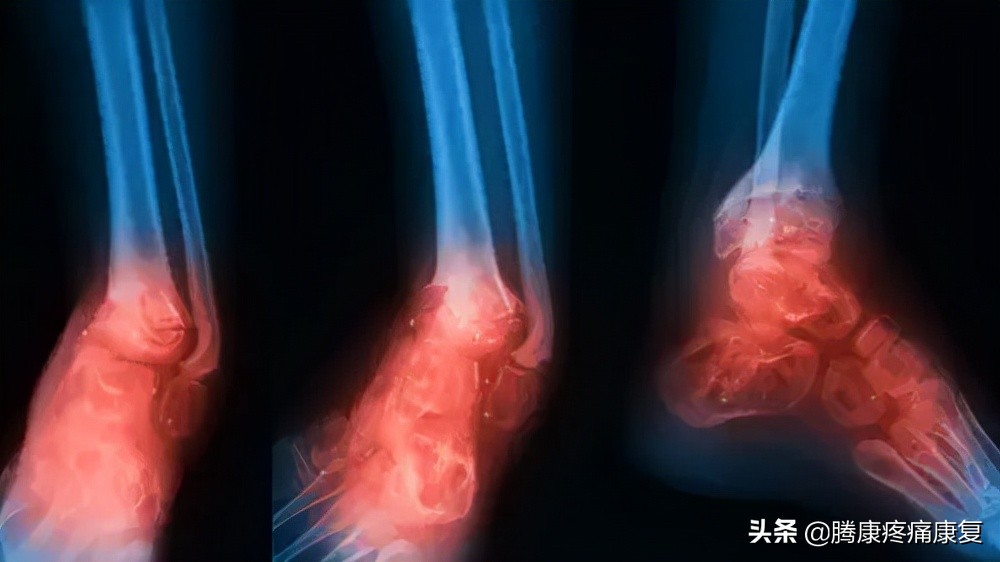

跟腱炎或断裂

跟腱是人体最大的肌腱,它位于腿部后侧,连接小腿肌肉和脚跟骨。

当肌腱受到刺激时,通常是由于过度使用,可能会感觉到腿后部的灼痛,通常就在脚跟上方。也可能有小腿疼痛和僵硬感,这就是众所周知的跟腱炎。

老人小腿疼痛是什么原因,脚小腿肌肉疼痛是什么原因

当跟腱肌腱撕裂时,腿后部可能会突然出现剧烈疼痛。腿可能很难承受任何重量。有些人在受伤时还会听到“砰”的一声。

小腿骨折

小腿的胫骨或腓骨骨折可能是由于摔倒或腿部外伤性打击(如车祸)引起的。

这种损伤可能导致严重的小腿疼痛,肿胀,行走困难或无法承受任何重量。